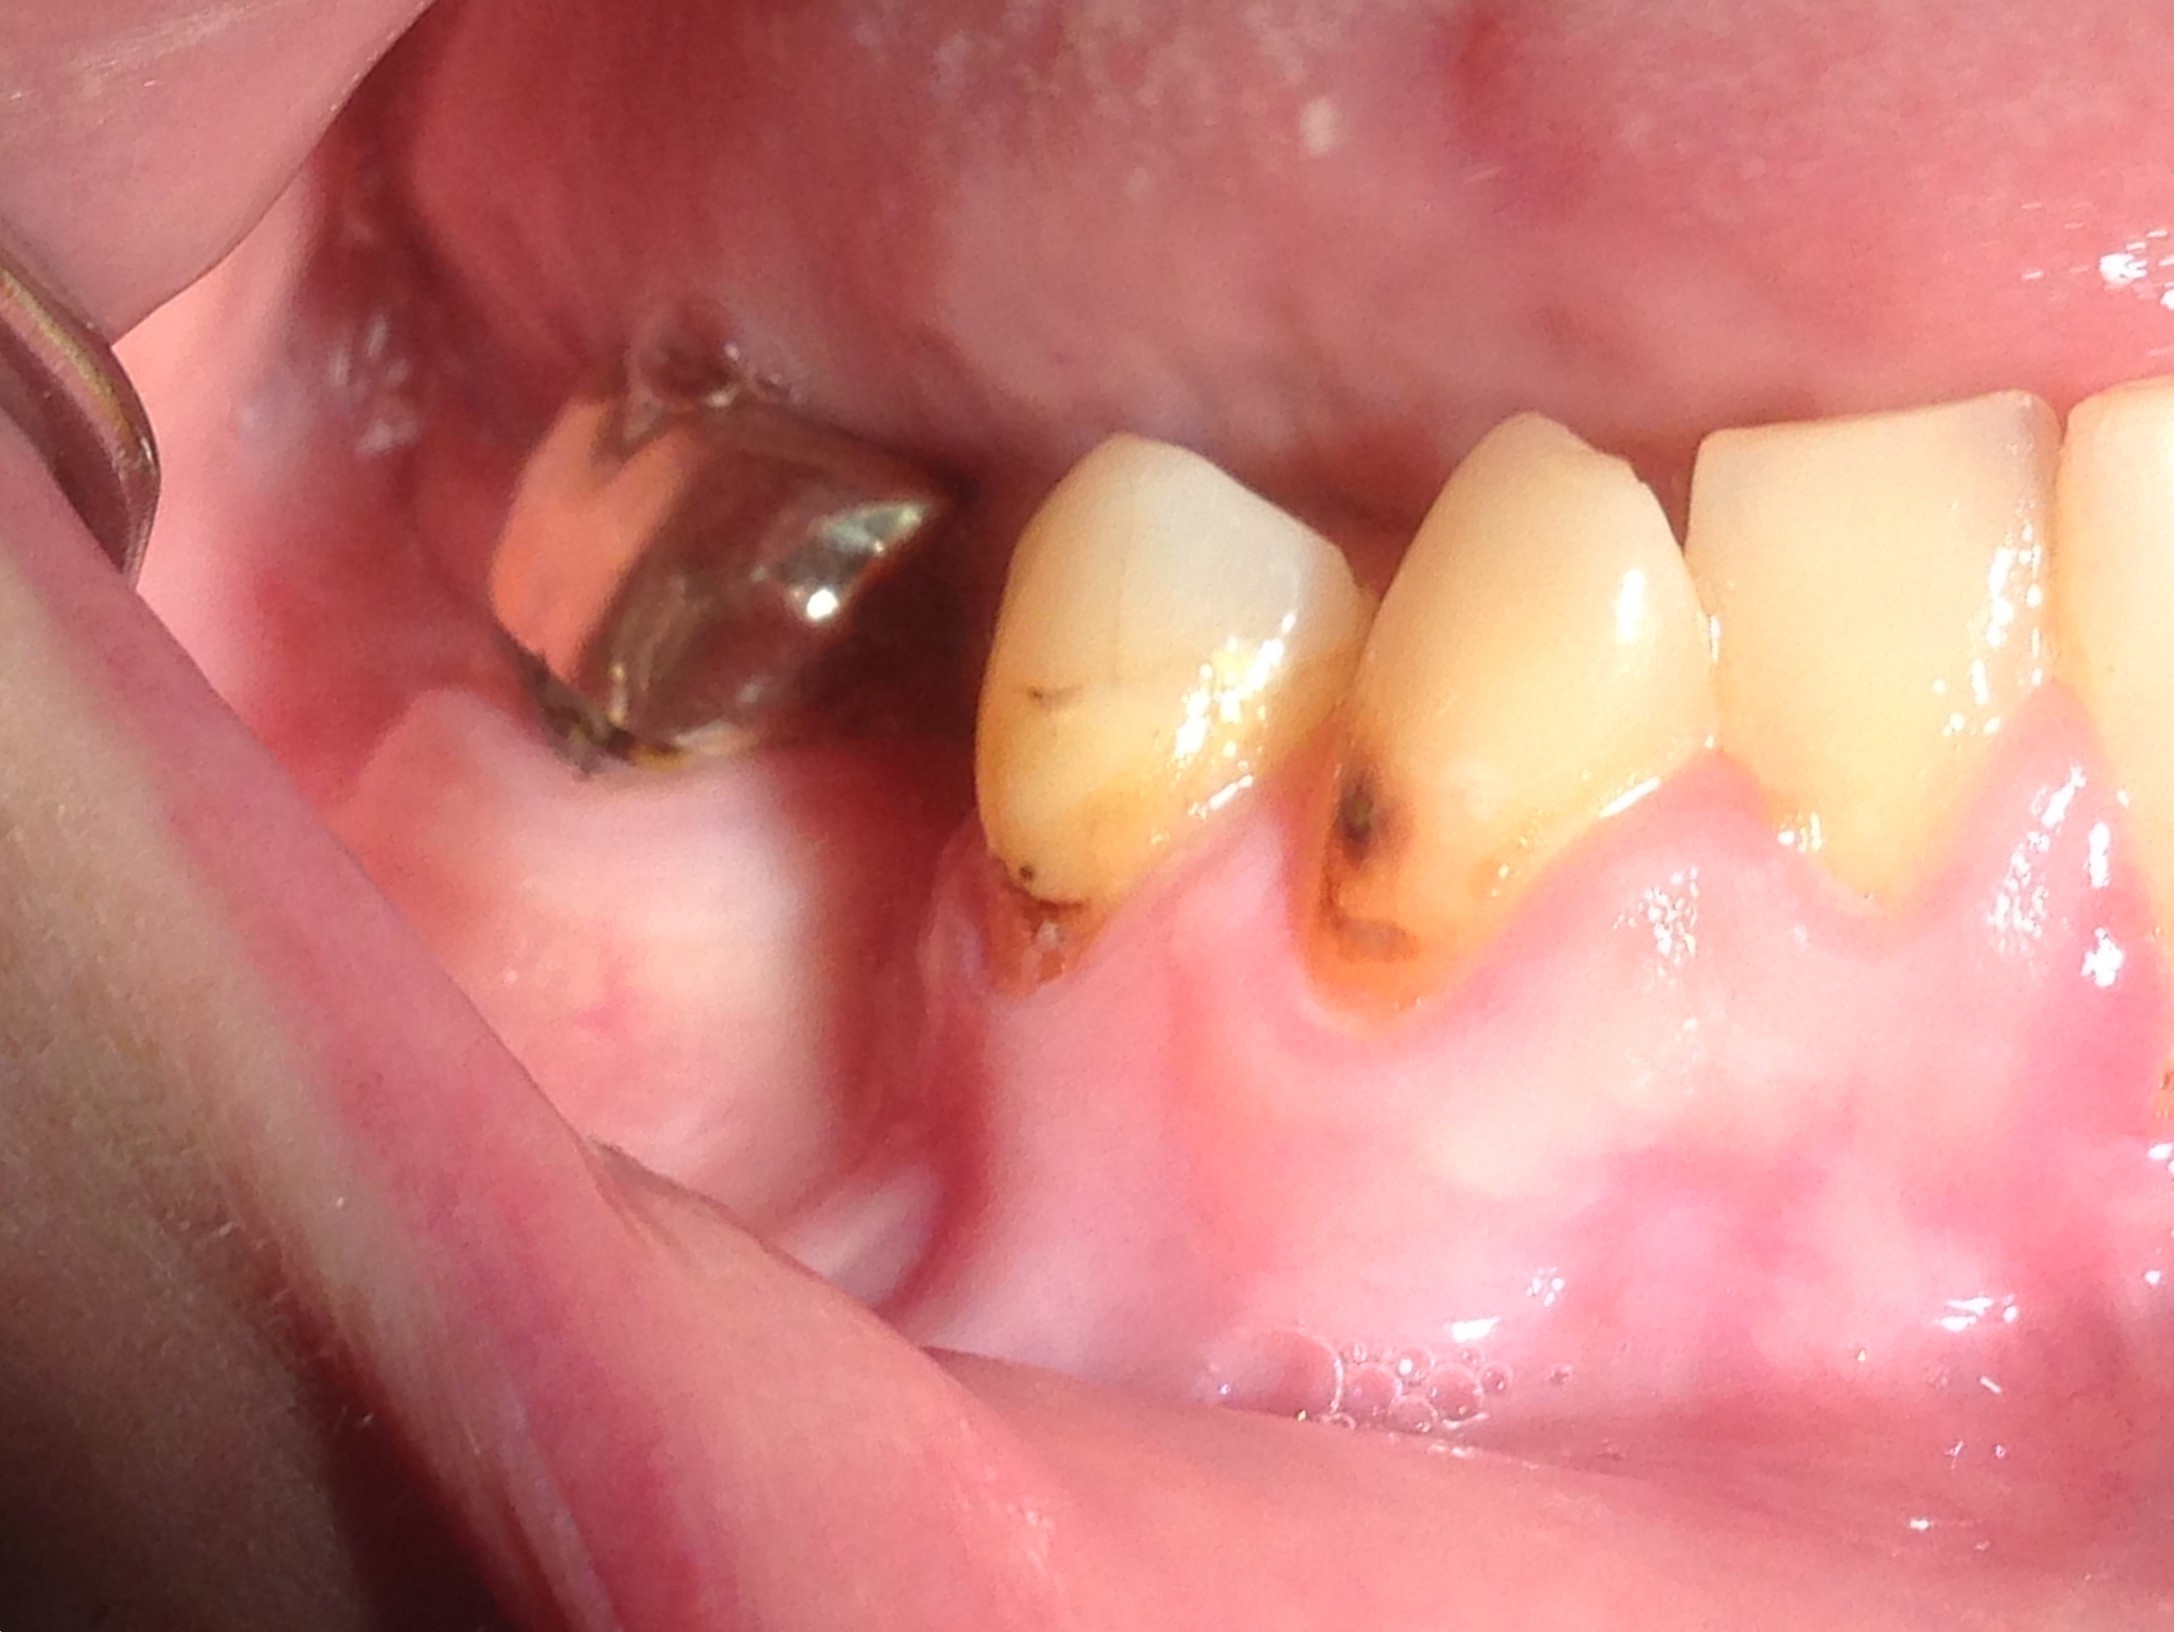

Often, the most visually striking manifestation of long-term meth use—known as “meth mouth”—is caused by the lack of saliva combined with an increase in soda drinking and extremely poor oral hygiene. This typically leads to meth abusers experiencing a large amount of caries. Decay begins with occlusal and facial caries and progresses rapidly, decaying to the bone level and often leaving only roots (Figure 1 through Figure 3).16

Fig 3. After 5 years of meth use in a 22-year-old male patient, cervical decay and coronal fractures were evident.

Figure 3

Fig 4 through Fig 6. Patient’s oral condition after 6 years of meth use.